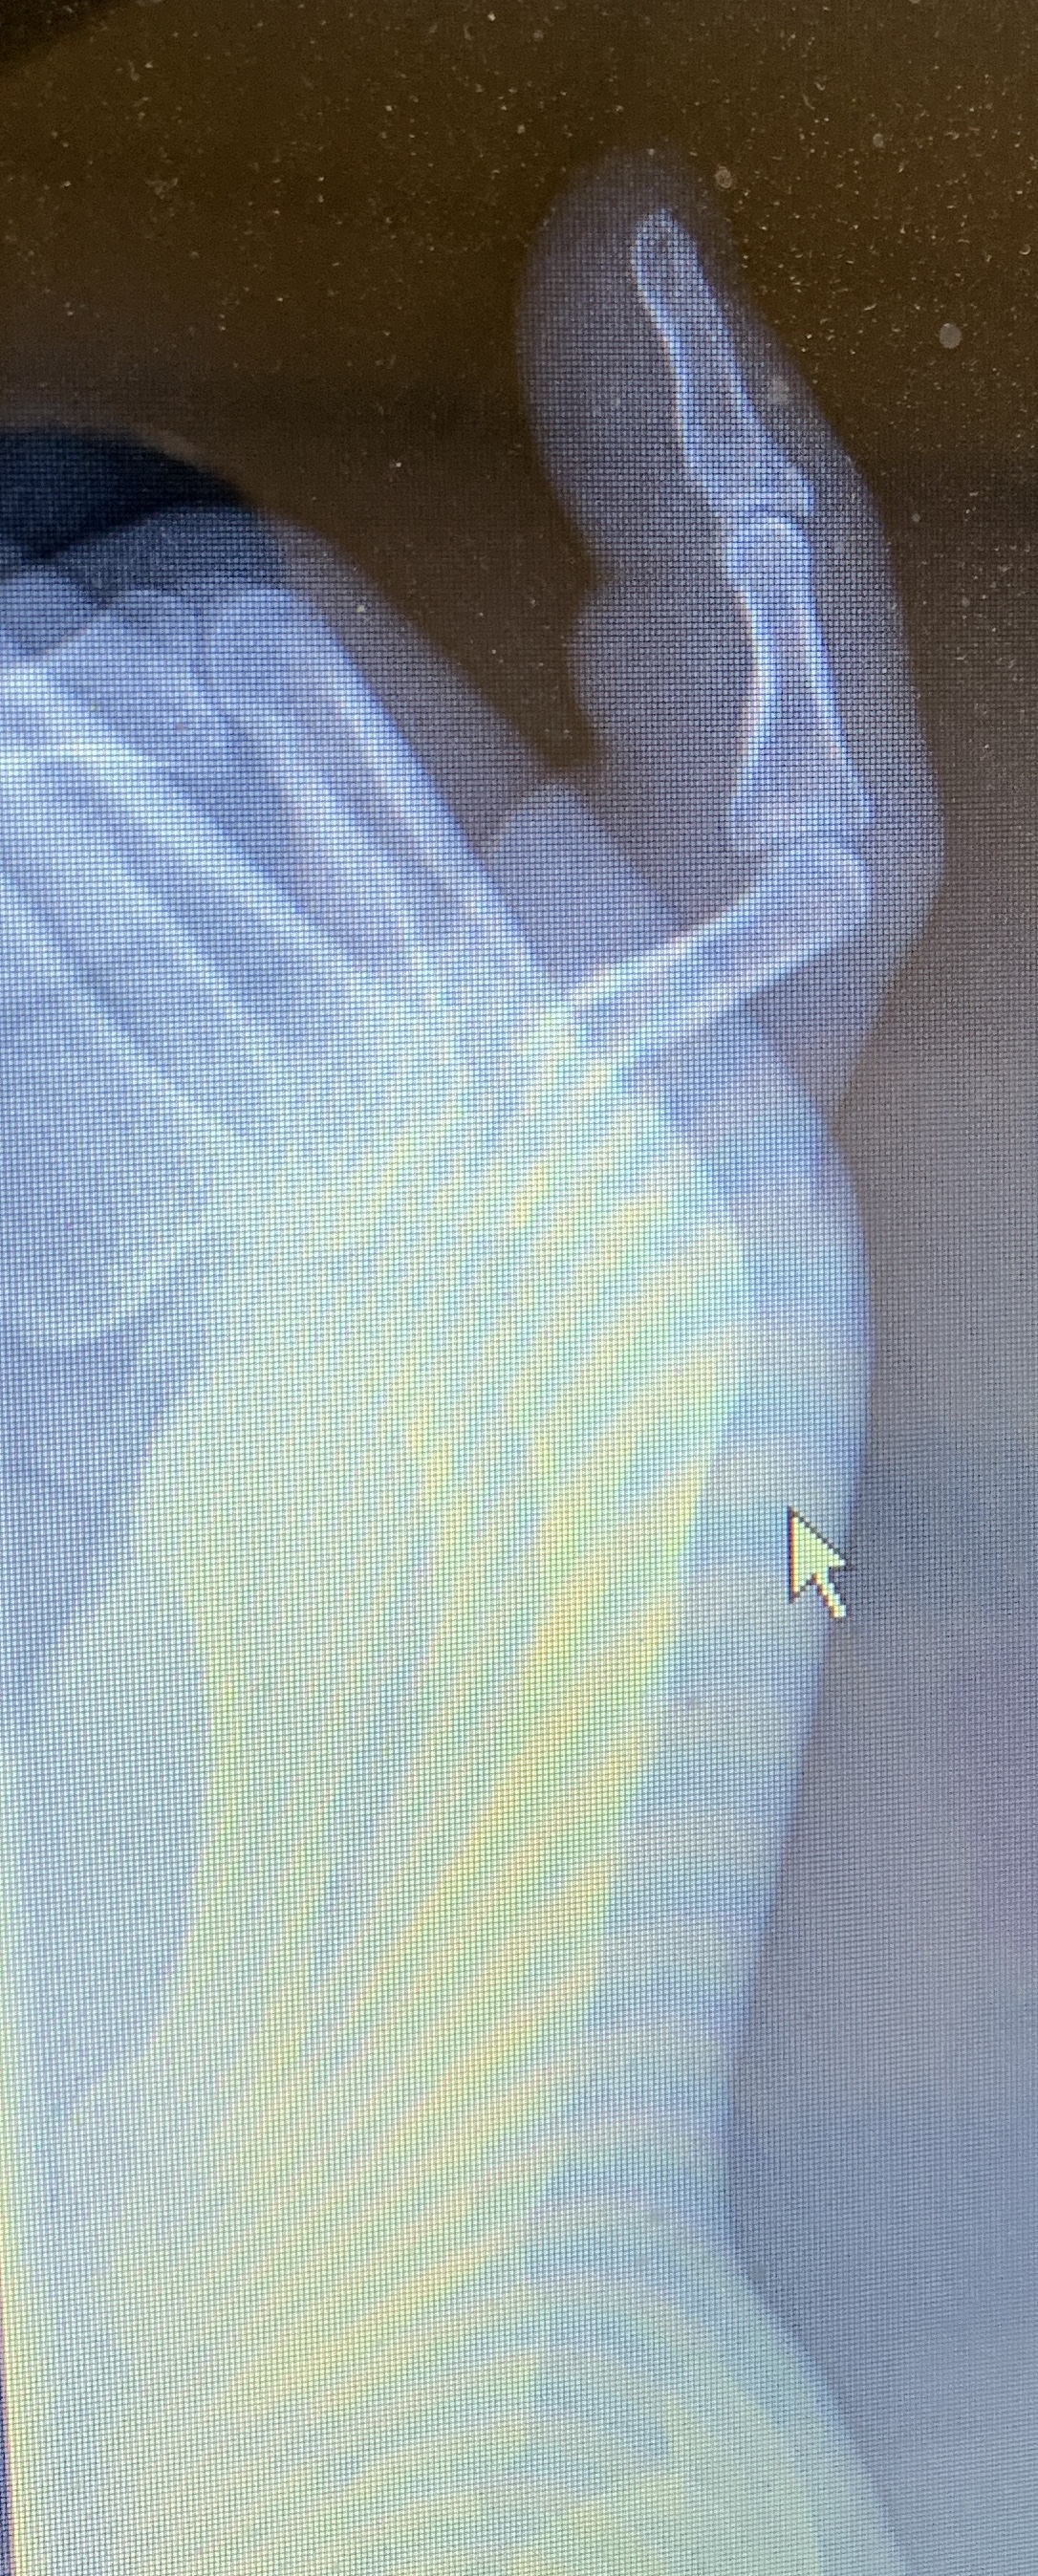

Om March 28, Oliver's Pinky got Gram-Schmidted during a fall near the Charles river. The transformation was reversed on April 5 by a hand surgeon: (the linearization was highly successful). Here is how things looked before the fix. The picture solves the riddle, why the finger was so much shorter before.

Oliver's Pinky